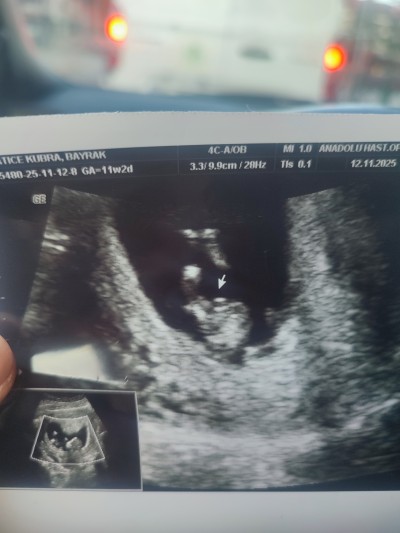

11 haftalık ve 13+5 haftalık ultrason görüntülerimiz doktor cinsiyette emin olamadi önce erkek sonra kız dedi ama sizin tahminleriniz neler?

Gebelik haftası 13+5